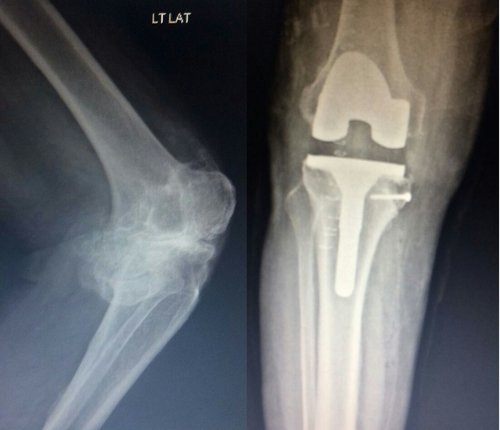

Outstanding outcomes of Bilateral Knee Replacement Surgery

65 year male patient with severe varus and flexion deformity in both knee,Knee society score -0 was severely disabled. Underwent a bilateral knee repl...